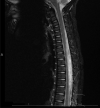

Case description: We report a case of spontaneous pediatric SEA in a 22-month old female without obvious neurologic deficit, who underwent a T10-11 decompressive laminotomy and evacuation of abscess and subsequent 3-week course of intravenous ceftriaxone for culture positive S. pyogenes.